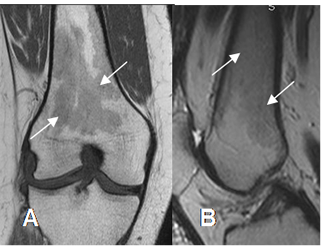

Fig 11. Persistencia de medula osea roja.

A: RM coronal en T1 y B: RM sagital en T2. Focos de medula roja (flechas) en el tercio distal del fémur, hipointensos en T1 y con SI intermedia en T2.